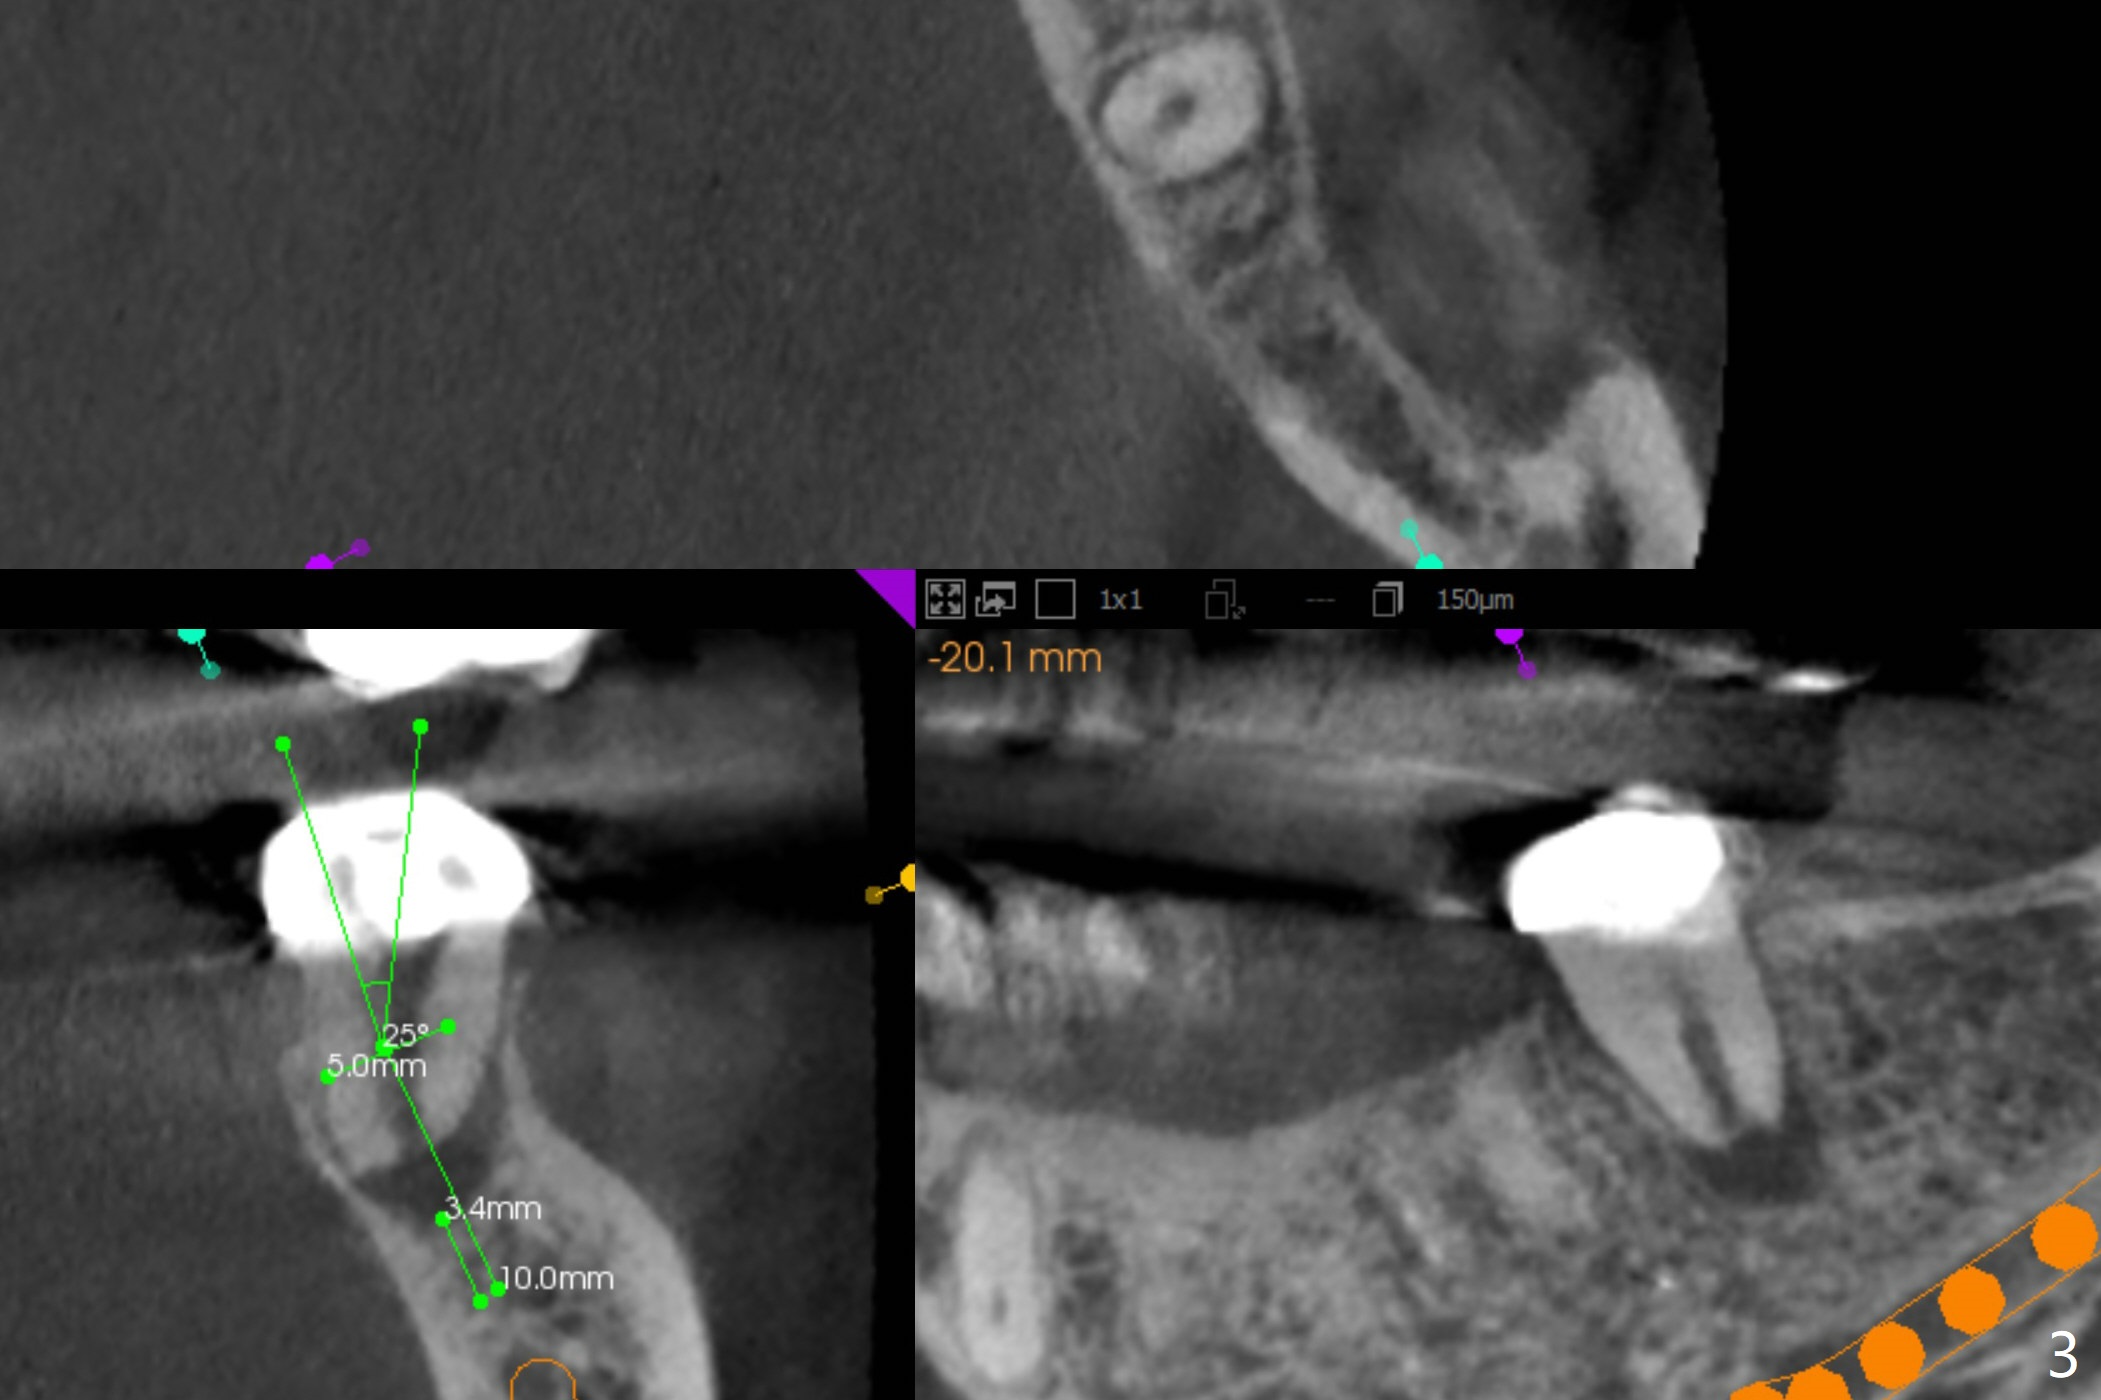

A 54-year-old woman will return for #18 extraction and implant 1 or 2 years post implants at #19 and #30. In fact the tooth has had incomplete RCT with PARL. Reanalysis of CT taken on 02/02/2017 (before RCT) shows that RCT retreatment should not be too difficult (Fig.1,2). If the treatment turns out to be not successful, a 5x10 mm immediate implant will be done with a possible 25 degree angled abutment (Fig.3,4).